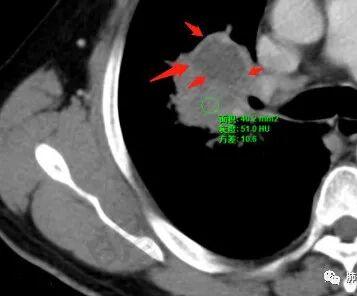

1、坏死区内寸草不生;2、病灶环形强化;3、远端树芽和结节;4、远端不是阻塞性炎症,而是树芽和结节,右肺上叶前后段都有,后段为主,而堵塞的支气管应该是前段;这些树芽的位置不是堵塞支气管的责任区;5、支气管不是突然截断堵塞,而是逐渐狭窄;6、纵隔淋巴结是椭圆形增大,内有坏死,不是肿瘤的圆形饱满;7、支气管周围粘液样坏死,符合仙人掌结核改变;

2、湖泊样坏死:这个病例其实不是湖泊样坏死。湖泊样坏死边界不清,周围有水草样改变;这个病例的坏死更像水库,不是湖泊,坏死区边界清楚,里面寸草不生;

3、阻塞性炎症:这个病例远端的散在病灶分布与责任支气管不符,所以不是阻塞性炎症,应该是树芽;

4、纵隔淋巴结肿大:这个病例的淋巴结肿大,不是圆形饱满,而是椭圆形,中间坏死。

所以,这个病例应先考虑炎性病变,以结核可能性大。慢性非特异性炎症伴脓肿形成,也可以这样的影像改变,但解释不了周围的树芽和结节。

再解释一下水库与湖泊的区别:

水库:是人工的,边缘是石头彻的大坝(环形强化类似大坝),坝缘没草长,边界清楚。

湖泊:是天然的,周围没有环形强化的大坝,是逐渐过渡到强化区的,边缘可有细小血管或者坏死不彻底的肿瘤区。